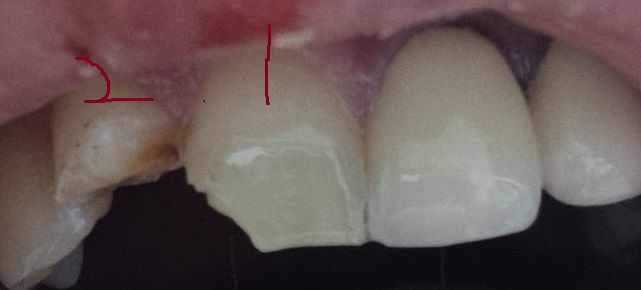

치아 사진에 보이는것처럼 넘어져서 앞니 2개가 저렇게 깨진 상태입니다

• 1번 째 사진